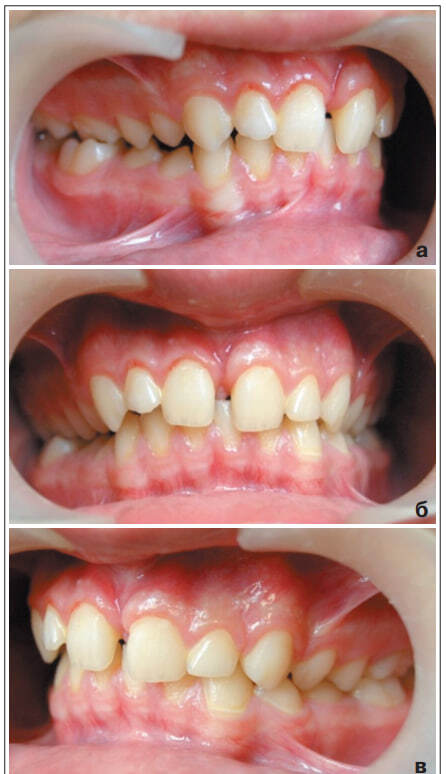

В этой связи искусственные зубы были сошлифованы, съемный аппарат оставлен для сохранения протяженности нижней зубной дуги в области премоляров. Продолжительность комплексного лечения и наблюдения за формированием прикуса у пациента Ф. А. составила четыре года. Иллюстративный материал (рис. 6, 7 и табл. 3) наглядно демонстрирует успешность примененной тактики лечения.

Рис. 6. Фотографии полости рта Ф.А., 13 лет, после прорезывания ретенированных 1.1, 2.1, 4.4 и 4.5 зубов: а – вид справа, б – вид спереди, в – вид слева

На ортопантомограмме, полученной после завершения активного периода ортодонтического лечения, имеются зачатки ретенированных сверхкомплектных зубов в области верхних и нижних клыков и премоляров слева. От удаления зачатков ретенированных сверхкомплектных зубов пациент отказался. В этой связи в настоящее время пациент находится под диспансерным наблюдением врачей ортодонта и хирурга-стоматолога. Таким образом, комплексный план лечения детей с множественной ретенцией комплектных и сверхкомплектных зубов включает ортодонтические и хируругические вмешательства, последовательность выполнения и объем которых определяется в соответствии с индивидуальными особенностями клинических проявлений патологии. При диагностике и лечении пациентов с аномалиями зубных дуг и окклюзии, осложненными ретенцией комплектных и сверхкомплектных зубов, целесообразно применение современных методов исследования, таких как ортопантомография, компьютерная томография, при которых лучевая нагрузка минимальна и не приносит вред здоровью пациента.